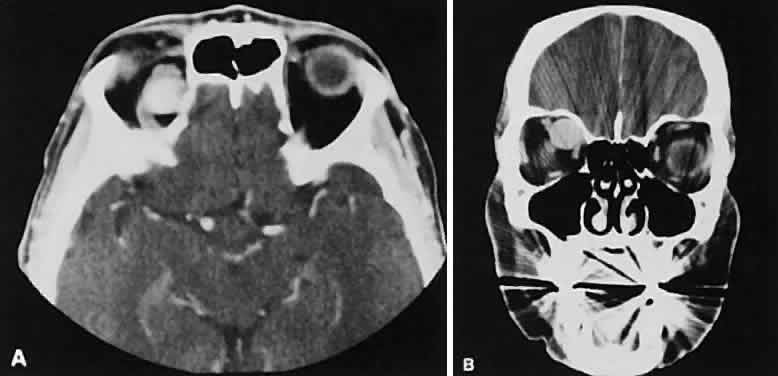

Optimal visualization of the orbit requires imaging from at least two planes. Axial slices should be oriented parallel to the optic nerve (-10 degreesto the orbitomeatal line) and no thicker than 3 mm. Axial views, because of volume averaging, may miss lesions located along the floor or roof. Additional views, typically coronal, can be obtained by reformatting data obtained during axial imaging or by direct coronal scanning.

Direct coronal views usually are preferable because of better resolution.6,7 They can be obtained by having patients lie either prone or supine, extending their neck, and angulating the gantry sufficiently to provide coronal imaging while avoiding artifacts from the teeth. Direct coronal scans also should be no thicker than 3 mm.

Coronal views may need to be reformatted from axial scans if a patient has extensive dental fillings, is anesthetized, or cannot extend the neck sufficiently for direct coronal scanning. The resolution on these images can be improved if data are collected from 1.5-mm contiguous axial slides.6 Spiral CT has resulted in improved multiplanar reformation with thin section (1 to 1.5 mm) axial images. High-resolution images necessary for leukocoria or foreign body imaging are obtained with 1-mm axial slices at 1:1 pitch at 1-mm intervals. Ideally, most screening orbit studies are performed at 3-mm direct axial and direct coronal images.

After the orbit has been visualized adequately, it also has been our practice to obtain 10-mm axial slices through the remaining portion of the head to complete the study. Intravenous contrast material usually is given, although the low-density orbital fat produces an inherent high level of contrast for most orbital CT studies. Intravenous administration of iodinated contrast medium is most helpful in detecting intracranial extension of an orbital process or identifying a pathologic process involving the optic nerve/sheath, most notably optic nerve sheath meningioma. Specific contraindications for contrast material include allergy or renal failure.

The extraocular muscles (EOMs), with the exception of the inferior oblique, originate from the anulus of Zinn in the orbital apex. The inferior oblique takes its origin from the frontal process of the maxilla and is seen occasionally on CT imaging. The superior oblique, after originating from the anulus, courses along the superior nasal orbital wall just above the medial rectus muscle before passing through the trochlea. The rectus muscles conveniently form a muscle cone, which is sometimes helpful in terms of differential diagnosis. Before thinner axial slices and multiplanar imaging were available, an enlarged inferior rectus muscle often was imaged as an apical mass, especially if dysthy-roid optic neuropathy was present. The importance of imaging from two different planes cannot be overemphasized in this situation.